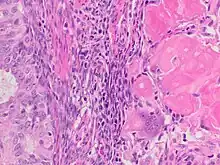

Histopathology

There is a three-tiered system for histologically classifying endometrial cancers, ranging from cancers with well-differentiated cells (grade I), to very poorly-differentiated cells (grade III).[23] Grade I cancers are the least aggressive and have the best prognosis, while grade III tumors are the most aggressive and likely to recur. Grade II cancers are intermediate between grades I and III in terms of cell differentiation and aggressiveness of disease.[58] There is also a separate "nuclear grade" system, where grade 1 tumors have inconspicuous cell nuclei, whereas grade 3 tumors have highly atypical nuclei.[59]

The histopathology of endometrial cancers is highly diverse. The most common finding is a well-differentiated endometrioid adenocarcinoma,[49] which is composed of numerous, small, crowded glands with varying degrees of nuclear atypia, mitotic activity, and stratification. This often appears on a background of endometrial hyperplasia. Frank adenocarcinoma may be distinguished from atypical hyperplasia by the finding of clear stromal invasion, or "back-to-back" glands which represent nondestructive replacement of the endometrial stroma by the cancer. With progression of the disease, the myometrium is infiltrated.[60]

A stage III endometrioid adenocarcinoma that has invaded the myometrium

A stage III endometrioid adenocarcinoma that has invaded the myometrium.jpg.webp) Metastatic endometrial cancer seen in a removed lung

Metastatic endometrial cancer seen in a removed lung_grade_1_endometrial_adenocarcinoma.png.webp) Grade 1: ≤5% solid non-glandular, non-squamous growth.[61]

Grade 1: ≤5% solid non-glandular, non-squamous growth.[61] Grade 2: >5% and ≤50% solid non-glandular, non-squamous growth.[61]

Grade 2: >5% and ≤50% solid non-glandular, non-squamous growth.[61] Grade 3: >50% solid non-glandular, non-squamous growth.[61]

Grade 3: >50% solid non-glandular, non-squamous growth.[61] Nuclear grade 1: Oval, mildly enlarged nucleus with evenly distributed chromatin.[62]

Nuclear grade 1: Oval, mildly enlarged nucleus with evenly distributed chromatin.[62] Nuclear grade 2: Intermediate features.[62]

Nuclear grade 2: Intermediate features.[62] Nuclear grade 3: Markedly enlarged and pleomorphic nuclei, with coarse chromatin and distinct nucleoli.[62]

Nuclear grade 3: Markedly enlarged and pleomorphic nuclei, with coarse chromatin and distinct nucleoli.[62] Squamous growth seen as necrotic “ghost cells” of keratinocytes at right in image, leaving pink keratin.

Squamous growth seen as necrotic “ghost cells” of keratinocytes at right in image, leaving pink keratin.